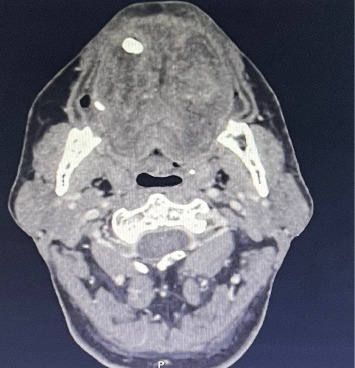

Angioedema of the tongue, also known as angioneurotic, or Quinke edema is a swelling of the tongue due to plasma leaking from capillary and postcapillary venules into deep submucosal tissue. This condition can either be hereditary, or acquired, due to allergy induced reactions for example. With an acute onset, this phenomenon can potentially be life threatening due to sudden and complete upper airway obstruction. Our aim is to describe the case of a 54-year-old schizophrenic male patient who presented with an angioedema of the tongue occurring after oral administration of haloperidol, a first-generation antipsychotic. The patient was admitted for close respiratory monitoring. The established cause for this condition was an allergic reaction to haloperidol. The following course was a favorable outcome with complete resolution of the edema without respiratory distress. We aim to report our case and to delve into other existing similar cases reported thus far in literature.

Abstract Image